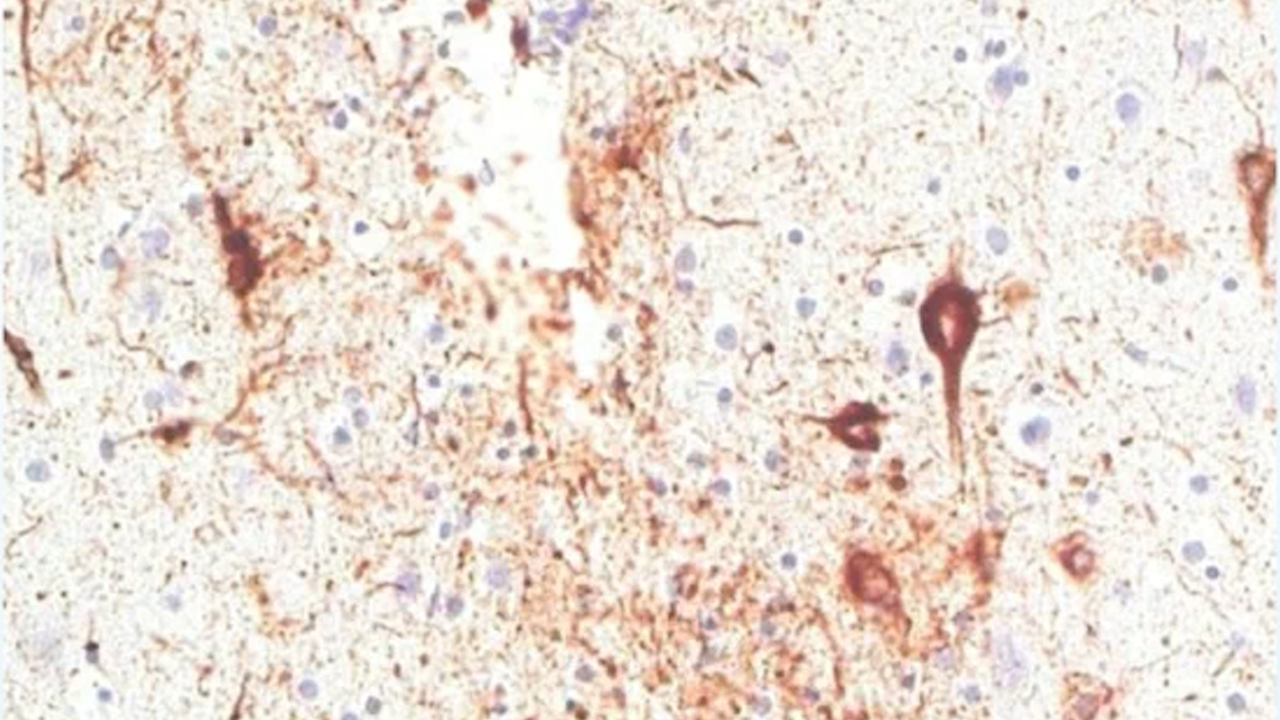

The clear picture below is of a healthy brain, while the one with the brown marks across it was Green's.

"That picture is a section of the brain stained for the abnormal tau protein. It's the abnormal tau protein accumulating in specific regions of the brain that defines CTE," Professor Buckland told Weekend TODAY on Saturday morning.

"The brown is the tau … (and) in the normal brain there's no brown at all. That's what you expect of someone of 49 and 50 (years-old) looking at the frontal cortex."

Paul Green's brain. The expert who studied Paul Green's brain after his death has revealed he suffered crippling CTEs. All the brown are CTEs.